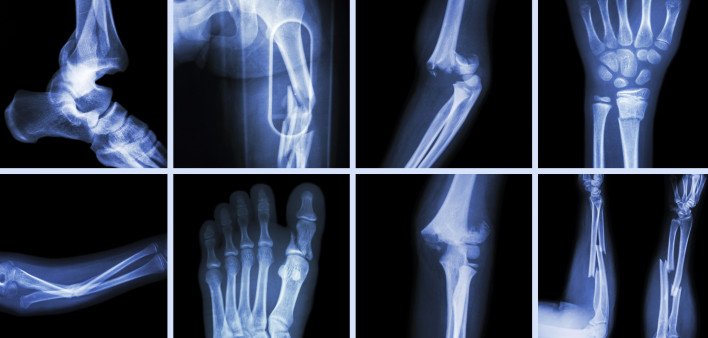

People living with HIV are more likely than their HIV-negative counterparts to experience fragility fractures, which occur as a result of minimal force and are often a sign of osteoporosis, or weakened bones. But what are the HIV-related risk factors, and can the likelihood of fragility fractures be measured? A $2.4 million grant from the National Institutes of Health will help two researchers at the Yale School of Medicine and the Yale School of Nursing develop a tool to assess the likelihood that a person with HIV will experience such fractures within a year.

Bone mineral density loss is a growing concern among people with HIV, especially those aging with the virus. Last year, researchers found that people with HIV had a 1.5-fold increased risk for any fracture and a nearly fourfold higher risk for a fragility fracture. What’s more, the loss of bone mineral density could explain only 15% of the increased risk for fragility fractures. To learn more, see “What’s the Skinny on Bone Health for People With HIV?”